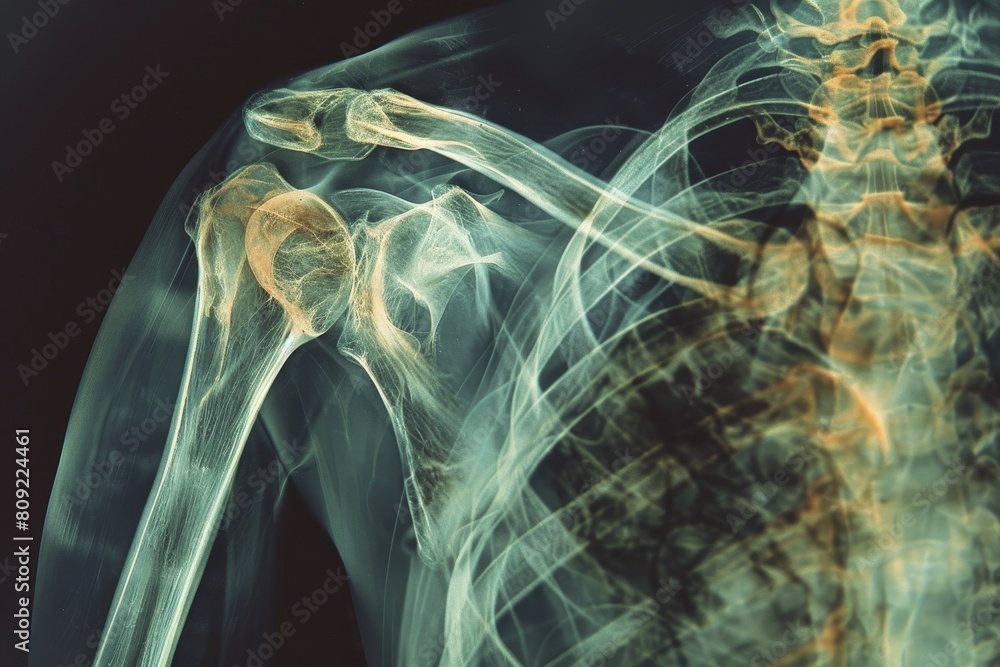

Xray showing the intricate structure of a persons shoulder area and Shoulder X Ray Abnormal Choosing a search strategy and utilizing it consistently is a helpful method to overcome common errors seen in diagnostic. The shoulder series is fundamentally composed of two orthogonal views of the glenohumeral joint including the entire scapula. How should i assess someone with a painful shoulder? Assessment of a person with. Last revised in november 2022. A normal shoulder x. Shoulder X Ray Abnormal.